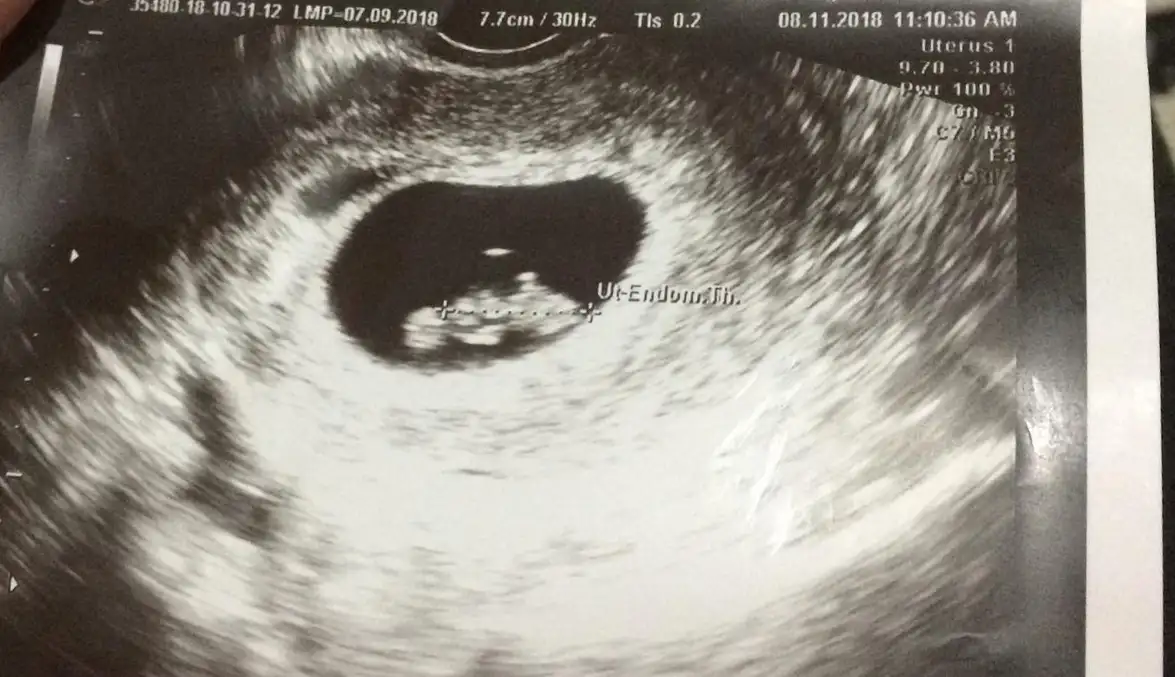

Bu arada hanımlar cinsiyet tahmini nasıl yapıyordunuz :))) bu ultrason fotoğrafı vajinal.elaine benes canım bak benim bugün kontrolüm vardı. Karından göremedi yine. Vajinal baktı. Ki 8. Haftadayız.

1,5 cm olmuşuz

Normalde özel hastaneye gidiyorum nolur nolmaz diye devlet hastanesine kayıt açtırmaya diye gitmiştim. Benim ilk gebelik hiç bilgim de yoktu geç gebelik 6+1 karından baktı kesenin içi boş gebelik olabilir kendini hazırla tarzında konuştu elim ayağım titredi odasında. Ondan merak ettim kim ne zaman ultrasonda gördü diye. Canım ultrason resmin ne kadar güzel çıkmış maşallahelaine benes canım bak benim bugün kontrolüm vardı. Karından göremedi yine. Vajinal baktı. Ki 8. Haftadayız.